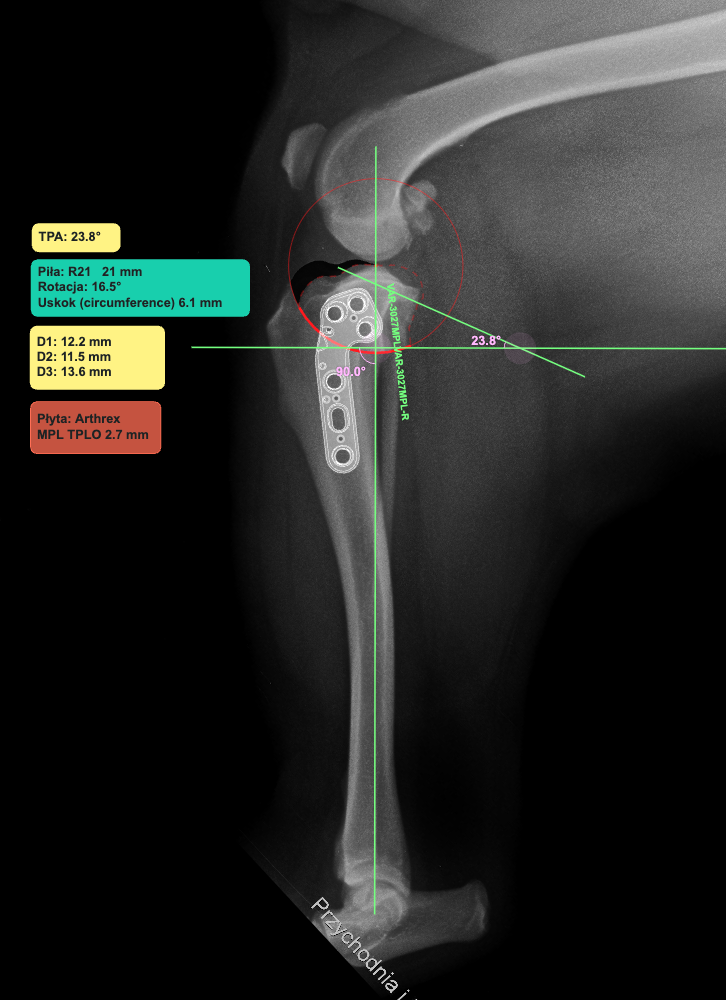

Standardem naszej Kliniki jest planowanie zabiegu z wykorzystaniem oprogramowania vPOP Pro. Pozwala ono na pomiary kątów stawu kolanowego i dopasowanie odpowiedniego rozmiaru piły, którą wykorzystujemy do cięcia kości piszczelowej, dobrania odpowiedniego rodzaju i rozmiaru implantu (płyty), rozmiaru śrub.

Płyty Securos PAX, Arthrex TPLO System, iWET TPLO System są implantami, które na codzień używane są w naszej Klinice